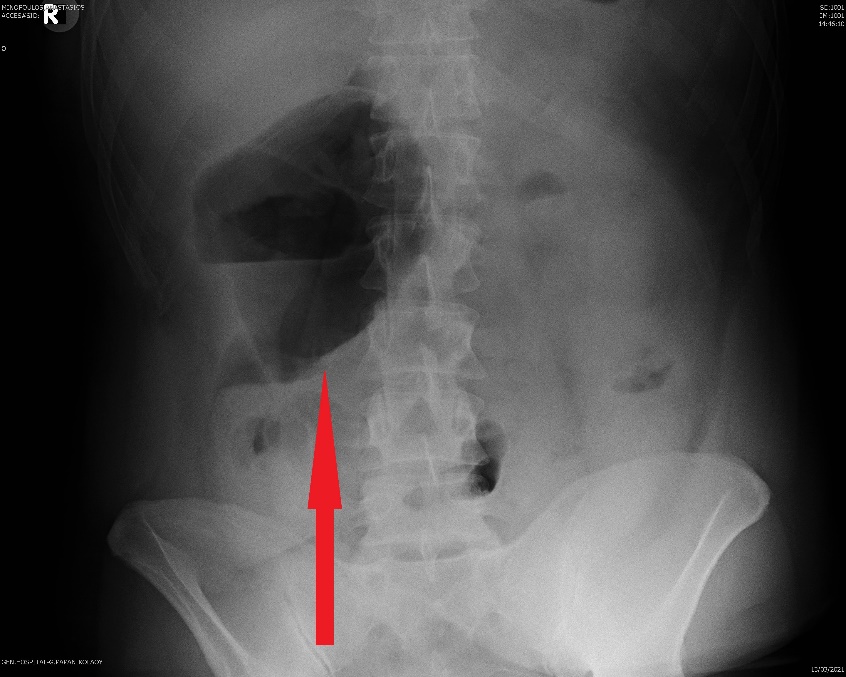

Παρουσία αέρα στο πυλαίο φλεβικό σύστημα, δευτεροπαθώς σε ισχαιμική κολίτιδα (Ευγενική παραχώρηση Dr. V. Penopoulos)